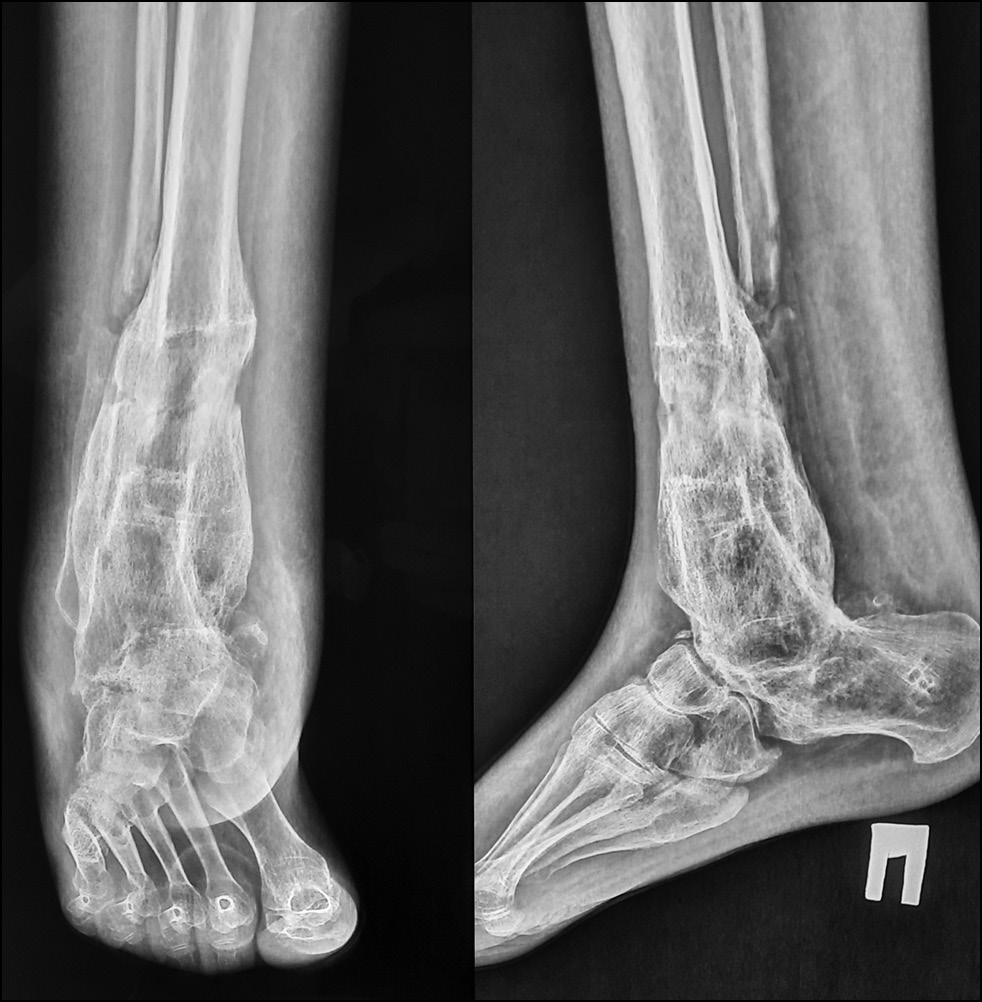

Рентгенологически выявлен спиралевидный перелом метафизарной зоны большеберцовой кости со смещением на стадии консолидации с образованием объёмной костной мозоли. Как и ранее, отмечались признаки снижения МПКТ (рис. 7, 8).

Рис. 7. Рентгенограмма в передне-задней проекции.

Fig. 7. X-ray image in anterior-posterior projection.

На момент повторного поступления в стационар отмечен дефицит 25-OH витамина D — 18 нг/мг (30–100) на фоне хронической болезни почек (ХБП), С3а (скорость клубочковой фильтрации — 49 мл/мин/1,73 м2), нормального уровня кальция, скорректированного на альбумин, фосфора, что сопровождалось гиперпаратиреозом (паратиреоидный гормон — 106,8 пг/мл (15–65)). По результатам двухэнергетической рентгеновской абсорбциометрии (денситометрии) МПКТ в проксимальном отделе бедренной кости выявлена остеопения до -2 SD по Z-score, до -1,7 SD в поясничном отделе позвоночника, остеопороз до -3,0 SD в лучевой кости.

Рис. 8. Рентгенограмма в боковой проекции.

Fig. 8. X-ray image in lateral projection.